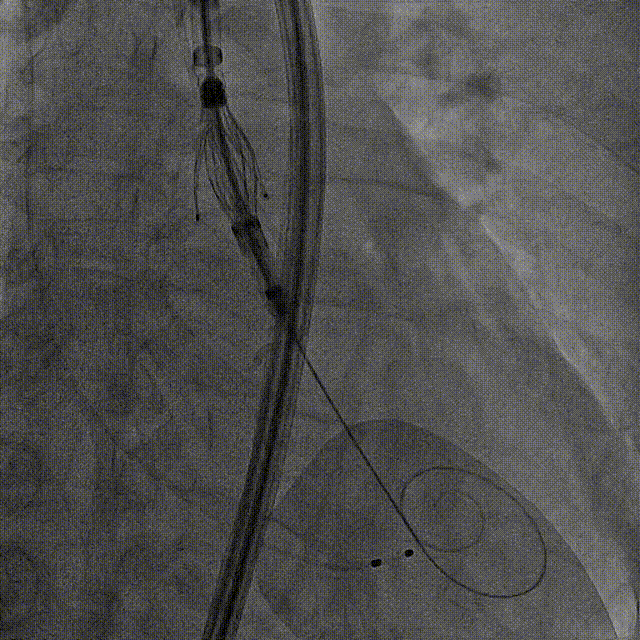

瓣膜调弯解离

定位键窦对齐验证

定位键入窦验证

深度检查

一键释放

后扩后造影